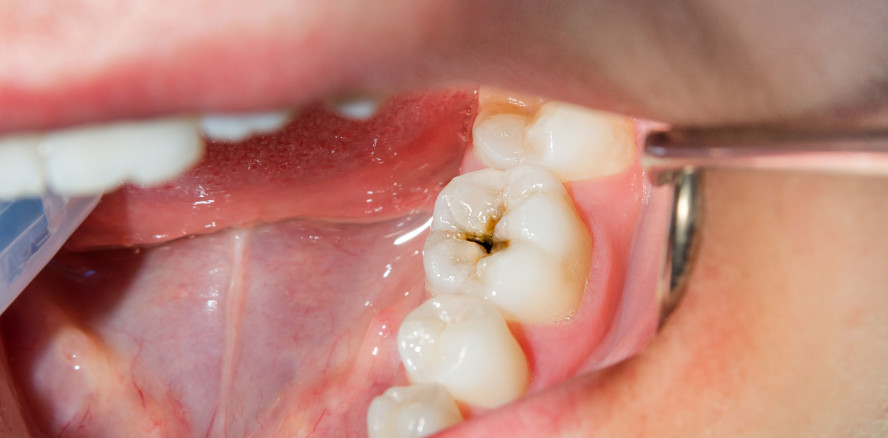

Mit einem umfassenden Update ist soeben die aktuelle Ausgabe des Jahrbuchs Zahnerhaltung erschienen. Das Kompendium vereint die beiden Kernbereiche Endodontie und Prophylaxe und liefert auf knapp 200 Seiten ein kuratiertes Best-of aus Wissenschaft, Praxis und Industrie. Klinische Fachbeiträge, aktuelle Marktübersichten sowie Einblicke in Trends und Innovationen machen das Jahrbuch zu einem unverzichtbaren Nachschlagewerk für Zahnärzte und Praxisteams.